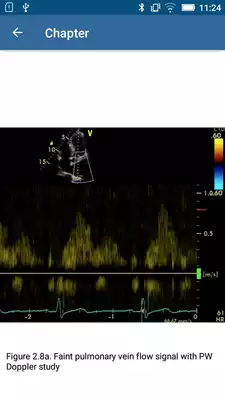

DESCRIPTION

Play this online game named Basic - Transthoracic Echocardiography.

This is the electronic course manual for registered participants of The Beyond BASIC - Transthoracic Echocardiography, The Chinese University of Hong Kong.Updates: